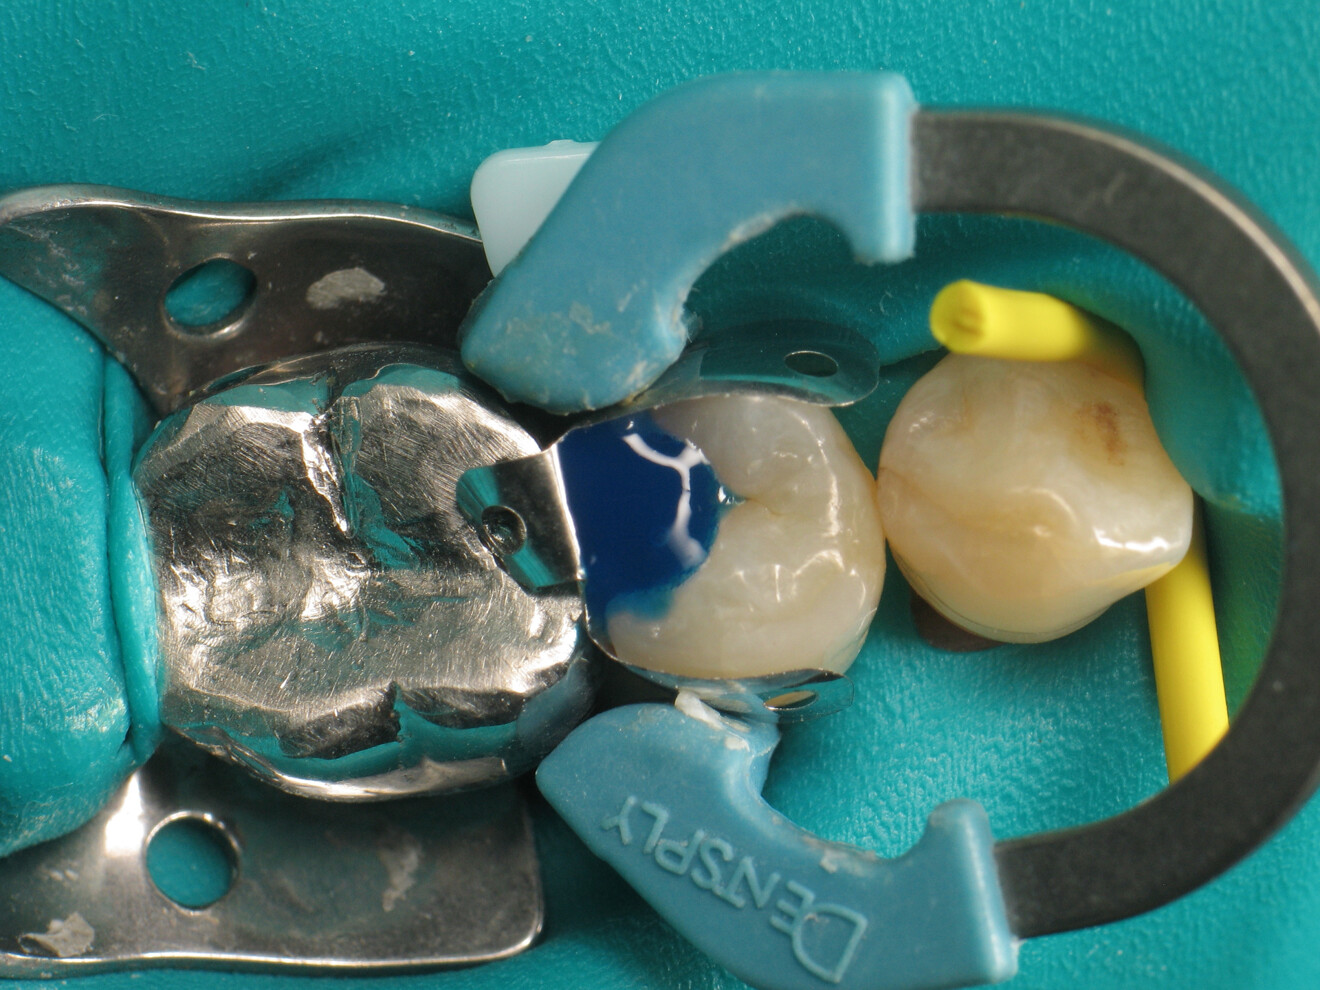

Fig. 1: Premolar with a Class II cavity. (Al images: Dr Yassine Harichane)

The clinical case described in this article concerns a Class II cavity in a premolar (tooth #45) restored using a thermo-viscous composite (Fig. 1). The tooth was isolated with a dental dam (Fig. 2). The cavity was then cleaned (Fig. 3). In order to obtain an anatomically correct distal wall, a matrix, a wedge and a ring were placed (Fig. 4). The tooth enamel was then etched for 30 seconds and the dentine for 15 seconds (DeTrey Conditioner 36, Dentsply Sirona; Fig. 5) and then rinsed and dried thoroughly (Fig. 6). Owing to the thinness of the remaining dentine, pulp protection (Telio Desensitizer, Ivoclar) was also applied (Fig. 7).

Fig. 5: Etching of the enamel and dentine.